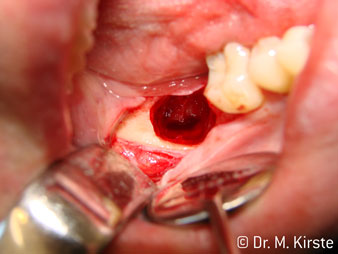

The 45° angle of the handpiece has been specially selected for its wide range of advantages. Colleagues who work in surgery, and for whom this handpiece was primarily developed, will soon appreciate the ability to work efficiently in very restricted spaces. In wisdom tooth extractions in particular (fig. 2) there is no need for large-scale spreading of the soft tissues in the cheek region (fig. 3). The design of the handpiece head combined with turning the head slightly during preparation allows work to be carried out quickly and safely in the retromolar region.

The professional design of the bearings inside the handpiece head guarantees quiet running of the bur; this makes for an impressively atraumatic cut in the separation of tooth and root (fig. 4-9).